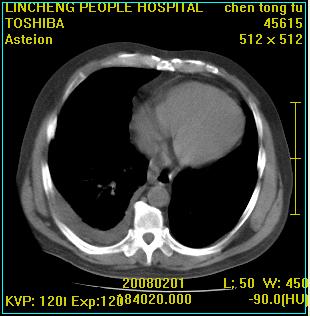

患者,男性,62岁。主因头晕,发热,咳嗽6天,高热达39度,esr19mm/h,wbc 3.9×10 9/l

右肺大叶性肺炎,胸腔积液。建议痰检。

考虑为右肺大叶性肺炎,胸腔积液,建议必要时纤维支气管镜检查,以排除肿瘤性病变。

右肺大叶性肺炎,胸腔积液,建议严格抗炎治疗后复查.